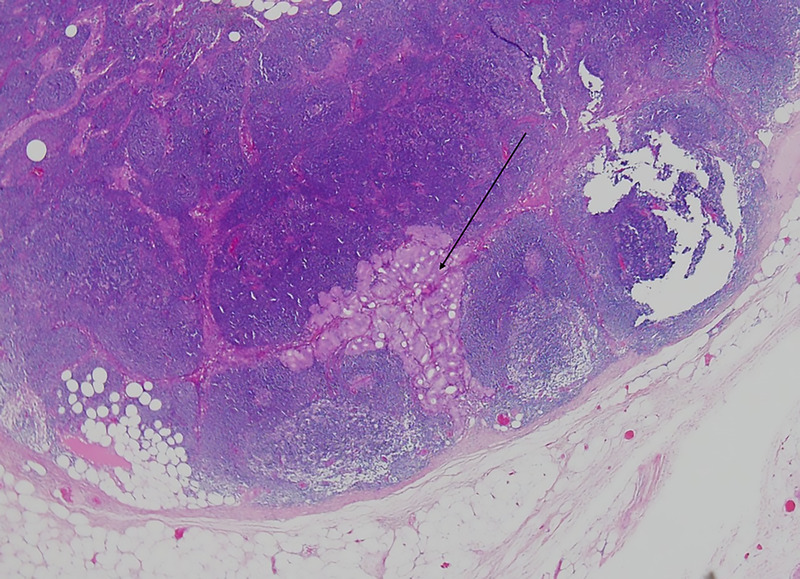

Results: A total of 70 patients underwent RP for intermediate (34 patients) or high-risk disease (36 patients). According to the Partin, MSKCC, and Briganti 2012 nomograms, positive LNs were expected in 7, 13, and 12 patients, respectively. At PLND, 1 positive LN was found in a single patient (p < 0.05 compared with the expected number of patients from all nomograms). Postoperatively, 10 patients developed detectable prostate-specific antigen levels. One patient exhibited radioligand uptake that could indicate LN involvement. Considering these 2 patients as failures, the negative predictive value of PSMA-PET/CT for LN involvement was 97.1%.